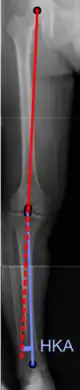

Varus or valgus deformity

There are two disorders relating to an abnormal angle in the coronal plane at the level of the knee:

- Genu valgum is a valgus deformity in which the tibia is turned outward in relation to the femur, resulting in a knock-kneed appearance.

- Genu varum is a varus deformity in which the tibia is turned inward in relation to the femur, resulting in a bowlegged deformity.

The degree of varus or valgus deformity can be quantified by the hip-knee-ankle angle,[33] which is an angle between the femoral mechanical axis and the center of the ankle joint.[34] It is normally between 1.0° and 1.5° of varus in adults.[35] Normal ranges are different in children.[36]

Hip-knee-ankle angle by age, with 95% prediction interval.[36]